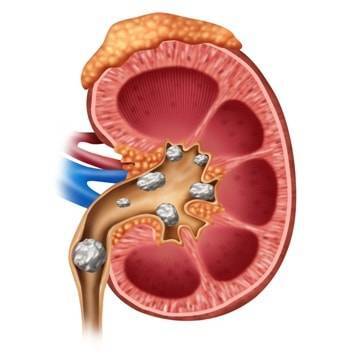

best urologist for kidney stones in vasant kunj

With experience in successfully treating more than 5000 urological stone patients, dr Bansal has helped more than 20 hospitals in and around Gurgaon in beginning minimally invasive/endoscopic laser procedures for kidney stone removal. He is proficient with laser/minimally invasive management of urological stones, prostate disorders, urological cancers, urethral stricture disease, male sexual disorders, and infertility. He has multiple national and international publications and has also authored textbook chapters.

With experience in successfully treating more than 5000 urological stone patients, dr Bansal has helped more than 20 hospitals in and around Gurgaon in beginning minimally invasive/endoscopic laser procedures for kidney stone removal. He is proficient with laser/minimally invasive management of urological stones, prostate disorders, urological cancers, urethral stricture disease, male sexual disorders, and infertility. He has multiple national and international publications and has also authored textbook chapters.